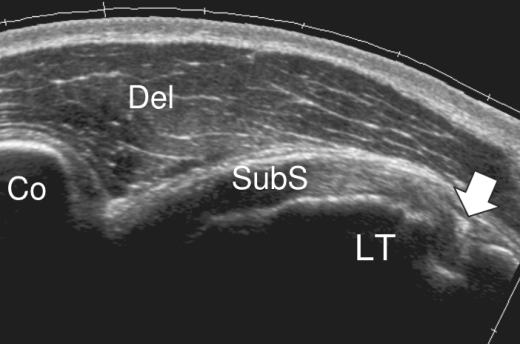

临床肌骨超声可针对性的进行神经、血管、韧带、肌肉、筋膜甚至半月板等骨关节结构的动态的直观观察,在肌骨超声的引导下,可客观准确的定位病灶并进行有效的处理。

科室目前已经全面开展了超声定位下的富血小板血浆注射技术(PRP)、局部封闭注射技术、高渗葡萄糖注射增生疗法、神经水分离治疗技术等。